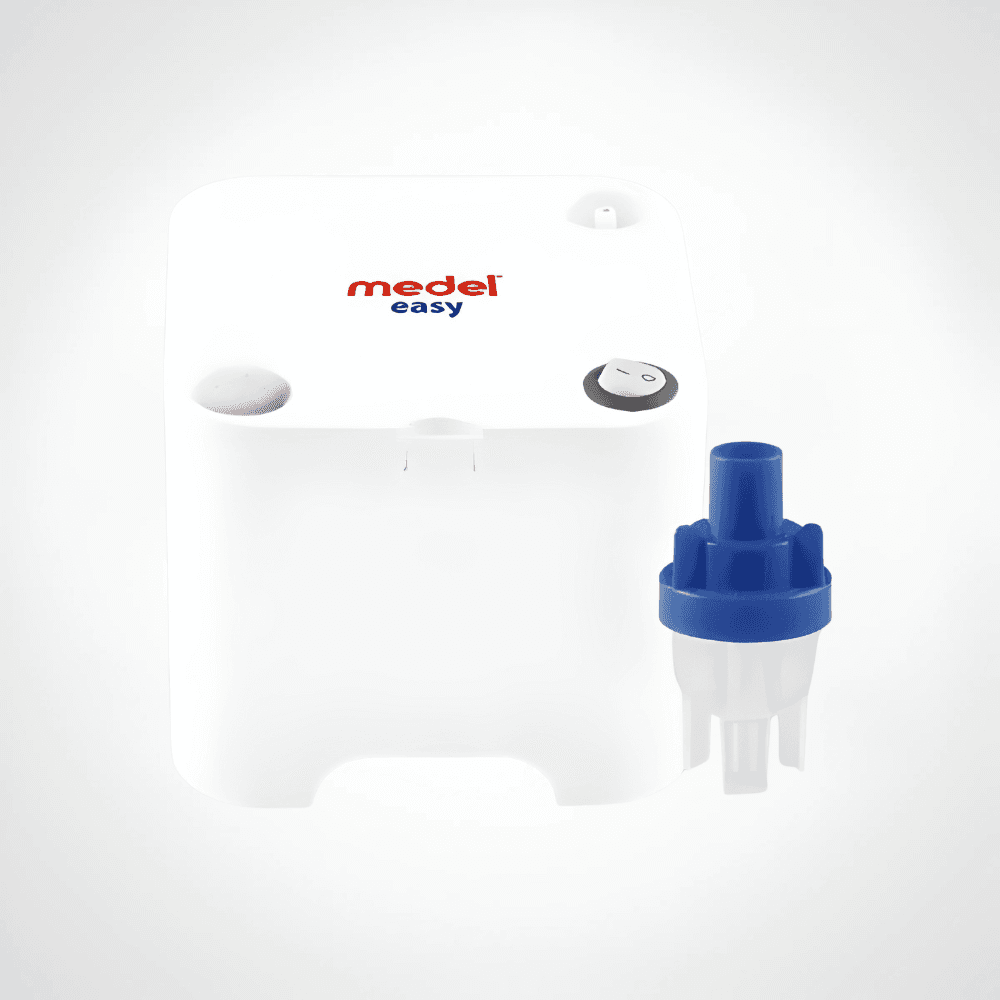

MEDEL Easy Aerosol – Nébuliseur Compact pour Inhalation et Traitement Respiratoire

Le MEDEL Easy Aerosol est un dispositif médical de haute qualité conçu pour faciliter les traitements inhalés à domicile. Grâce à sa technologie de nébulisation performante, il transforme le médicament liquide en fines particules pour une pénétration profonde dans les voies respiratoires. Compact, ergonomique et facile à utiliser, il est idéal pour toute la famille, des enfants aux adultes.

📋 Caractéristiques détaillées

| Caractéristique | Détail |

|---|---|

| Marque | MEDEL |

| Modèle | Easy Aerosol |

| Type d’appareil | Nébuliseur à compresseur |

| Technologie | Nébulisation pneumatique |

| Taille des particules | MMAD env. 3 μm |

| Débit de nébulisation | 0,3 ml/min (selon le médicament) |

| Alimentation | Secteur (220–240 V) |

| Accessoires inclus | Masque adulte, masque enfant, embout buccal, tuyau, ampoule de nébulisation |

| Poids | Environ 1,3 kg |

| Garantie | 2 ans |

| Normes & Certifications | CE Médical, ISO 13485 |

| Pays de distribution | Tunisie |

Le MEDEL Easy Aerosol est la solution idéale pour les patients souffrant d’asthme, de bronchite ou d’autres affections respiratoires. Alliant efficacité, confort et qualité médicale, il permet de suivre un traitement en toute sérénité à domicile.

Disponible dès maintenant en Tunisie sur votre parapharmacie en ligne – offrez à vos poumons la respiration qu’ils méritent !